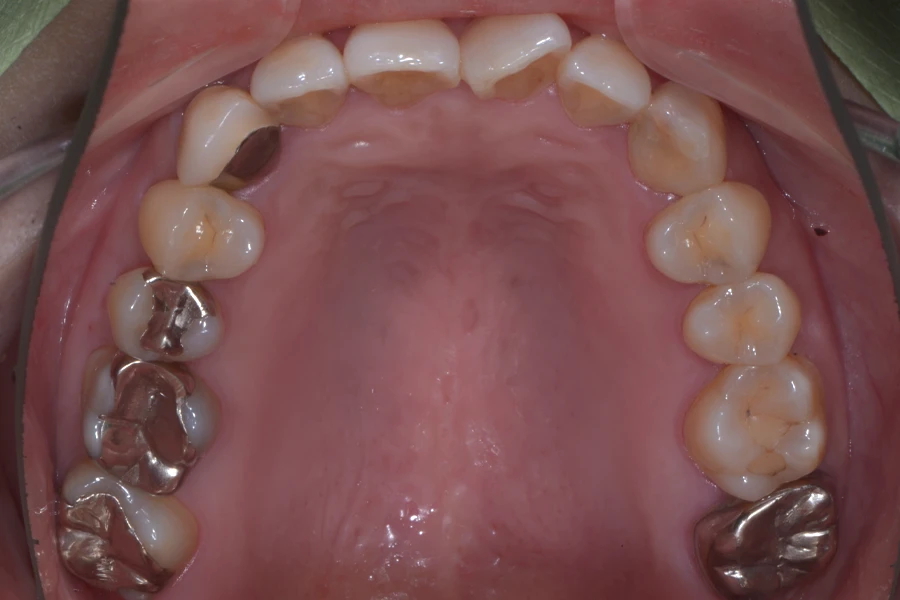

【30代女性】

一本だけ捻じれて

飛び出している

前歯を引っ込めたい

• 治療前

主訴 一本だけ捻じれて飛び出している前歯を引っ込めたい

期間 8か月

費用 35万円(別途調整料)

治療内容 上顎リンガル矯正(裏側矯正)

治療に伴うリスク 後戻り